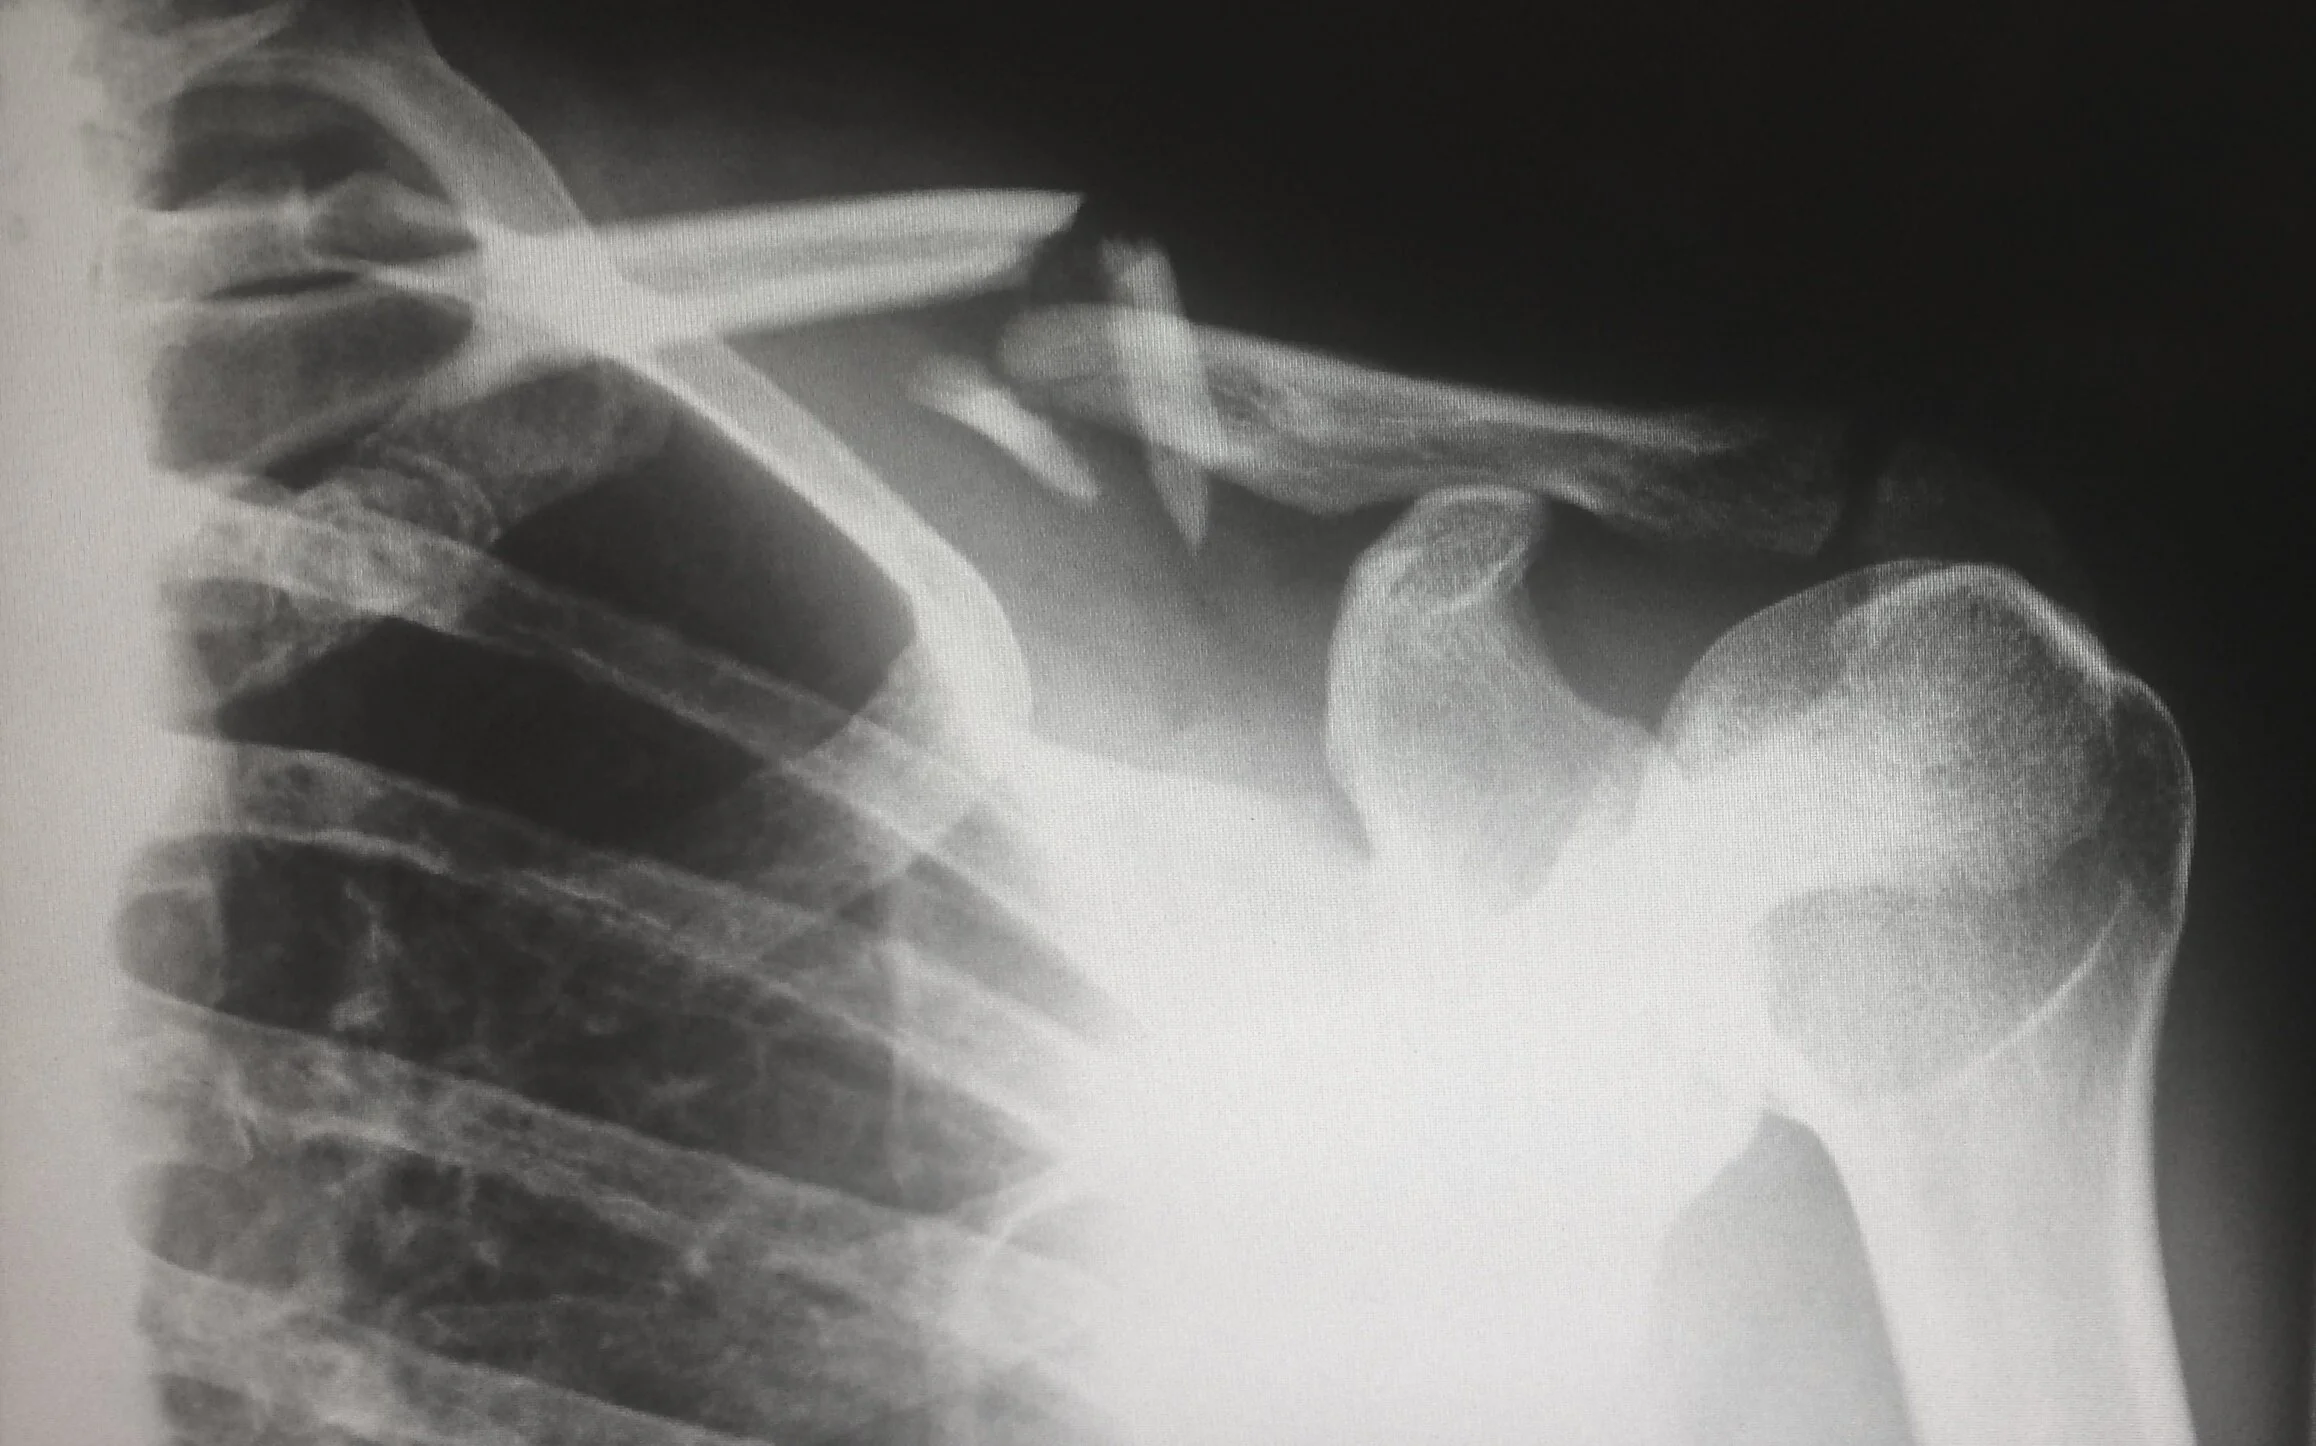

traumatisme

Après une chute, une fracture, une entorse la kinésithérapie est là pour vous soulager, récupérer et redonner de la souplesse.